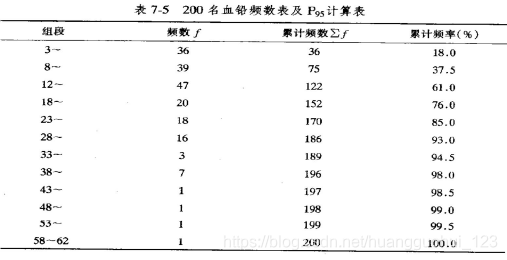

例2 某年某市调查了200例正常成人血铅含量(μg/100g) 如下,试估计该市成人血铅含量的95%医学参考值范围。

分析:血铅的分布为偏峰分布,且血铅含量只以过高为异常,要用百分位数法制定单侧上限。